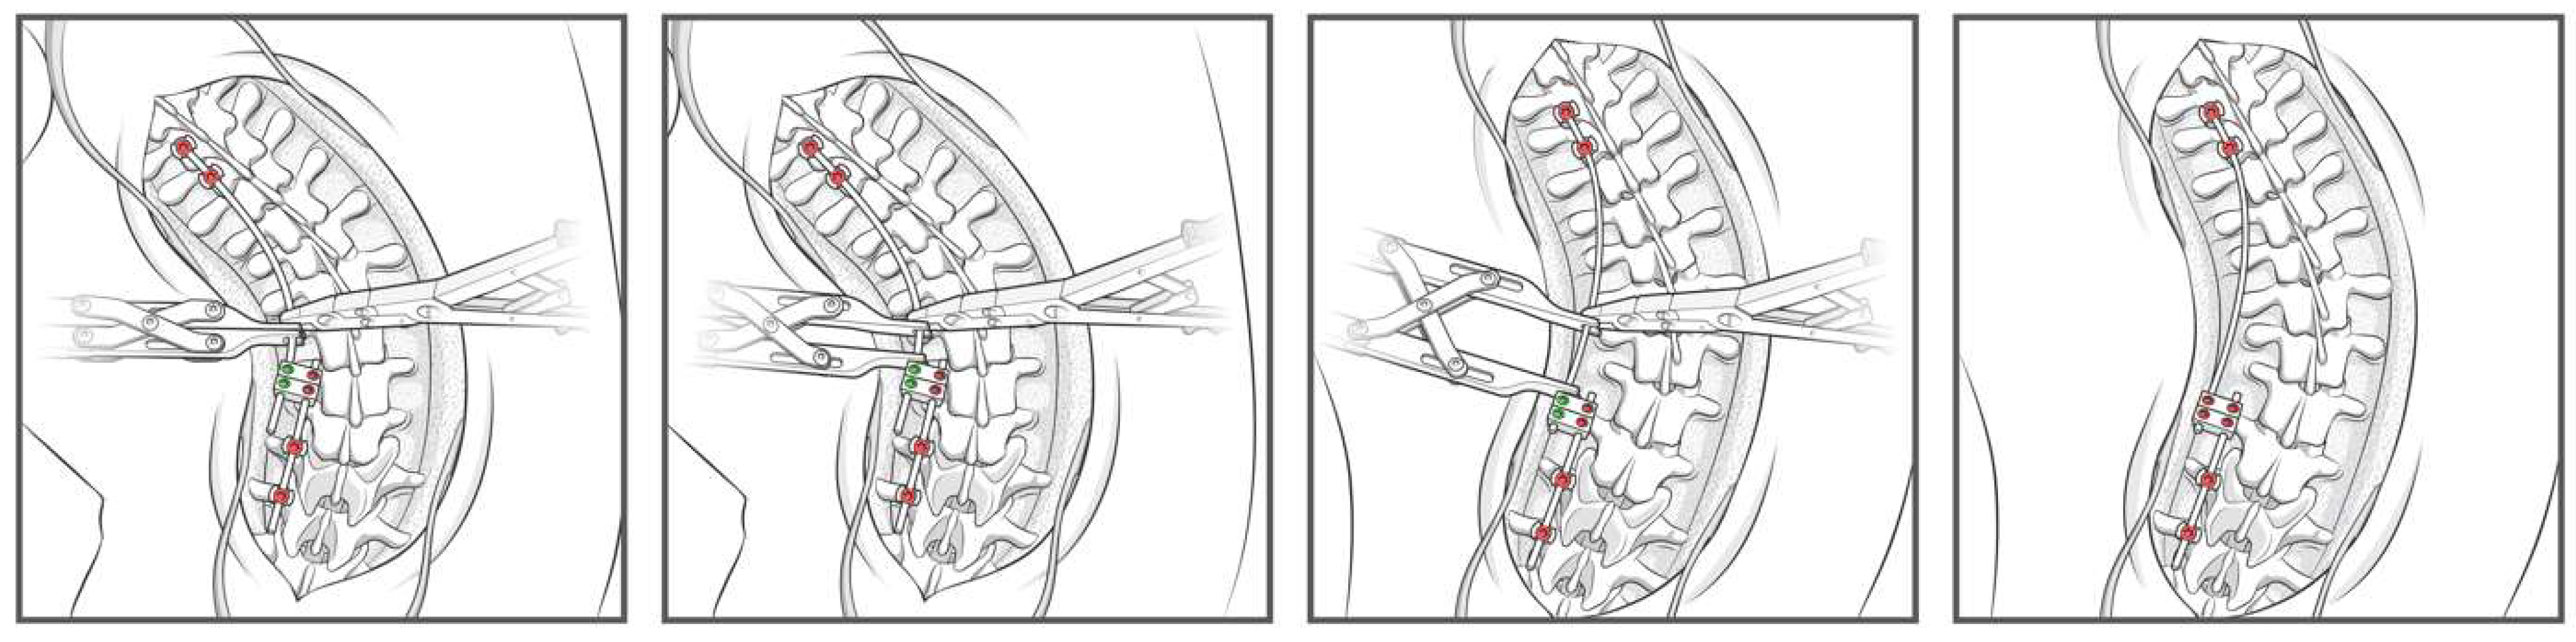

Figure 3.

Step-by-step schematic of the construct-to-construct internal distraction technique. The green caps represent loose set caps. Red caps represent tight set caps.

Schematic of the construct-to-construct internal distraction technique with proximal anchor points at thoracic ribs using upgoing rib hooks.

Figure 5.

Intraoperative X-ray showing a construct-to-construct internal distraction technique with an iliac screw serving as the distal anchor point and the last thoracic rib serving as the proximal anchor point (A). Intraoperative photo showing the iliac screw to thoracic rib setup before distraction is performed (B).

3.3. Traditional Growing Rods

The construct-to-construct internal distraction technique is the most common configuration for traditional growing rod constructs (Figure 6). The distal anchor points comprise two-level pedicle screw fixation. The last spinal level will represent the lower instrumented vertebra of the final fusion construct. The proximal anchor points may be either upgoing rib hooks or pedicle screws. We prefer pedicle screw fixation at upper instrumented vertebra, upper instrumented vertebra-1, and occasionally upper instrumented vertebra-2. It is important to keep in mind that these proximal pedicle screws will experience significant distraction forces with serial lengthening that could loosen the screws at the time of the final spinal fusion. A long titanium rod is passed under the muscle layer to engage into the proximal anchor points. The distal segment of this rod is connected to a lateral domino connector with significant overlap to allow for serial distraction in the future. A shorter rod is tunneled through the domino connector and engaged to the distal anchor points. A rod gripper is used to engage the longer, proximal rod approximately 1 cm above the domino connector (Figure 3). The set cap on the domino connector is loosened, and a distractor is placed between this connector and the rod gripper. Gradual distraction is applied in a controlled, “click-by-click” manner before the set cap is tightened to hold the correction.